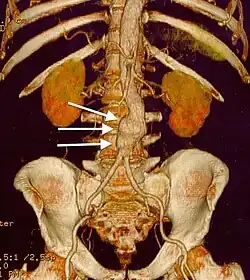

| CT reconstruction image of an abdominal aortic aneurysm (white arrows) | |